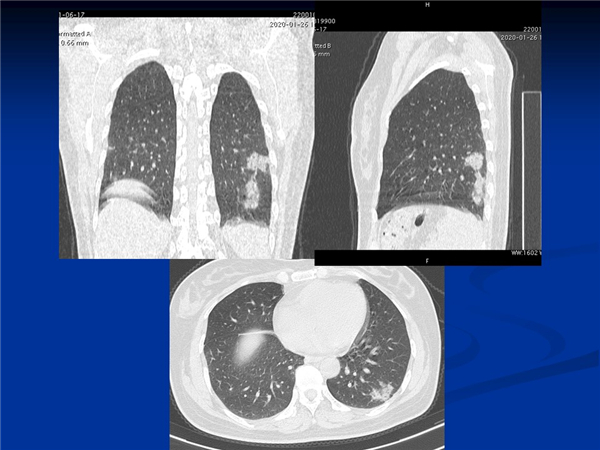

【病例分享】新型冠狀病毒感染肺部CT影像4例(常德市第一人民醫(yī)院)

幻燈片7.jpg